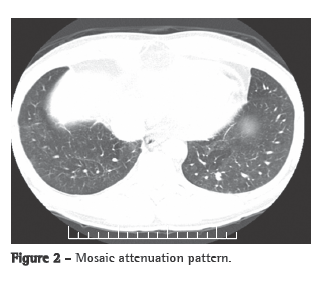

A transthoracic Doppler echocardiogram, which had been performed previously, showed moderate right heart enlargement, and pulmonary artery systolic pressure (PASP) was estimated to be 76 mmHg. A transesophageal echocardiogram demonstrated extensive thrombosis in the pulmonary artery trunk and PASP of 57 mmHg. Ultrasonography of the lower limbs revealed no signs of deep venous thrombosis. Lung perfusion scintigraphy, which was performed during hospitalization, showed low uptake in the view of the anterior and the apical-posterior segments of the left lung. The right lung was not visualized. Angiotomography of the chest revealed a large filling defect in the mediastinal and pericardial portion of the pulmonary trunk and arteries, there being enhancement of that defect after intravenous administration of contrast material (Figure 1a). In addition, there were predominantly peripheral nodules on the left (Figure 1b), as well as thickening of interlobular and peribronchovascular septa on the right, associated with upper lobe consolidation, moderate pericardial effusion and a mosaic attenuation pattern (Figure 2).

The clinical profile, together with the age of the patient, the failure of anticoagulant treatment, the tomographic alterations and the contrast enhancement, led to the hypothesis of intimal sarcoma-angiosarcoma-with pulmonary metastases. A CT-guided transthoracic biopsy of the left lung nodule was required. The specimen obtained consisted of a soft, reddish-tan filiform fragment, measuring 1.2 cm in length.

The case reported here draws attention to the need to raise the differential diagnosis in patients who are unresponsive to the current treatment of venous thromboembolism. Intimal sarcoma of the pulmonary artery is among the alternative diagnoses. Since iodinated contrast enhancement (angiotomography of the chest) can confirm the presence of the mass as well as its central location in the pulmonary trunk and arteries, which strongly suggest a diagnosis of intimal sarcoma of the pulmonary artery rather than that of CPTE, it constitutes a clue for making the former diagnosis. We emphasize the need for the proper use of the clinical methods currently available for the exact etiological definition of arterial pulmonary hypertension, prior to prescribing new medications (phosphodiesterase-5 inhibitors and inhibitors of endothelin receptors).(8,16)